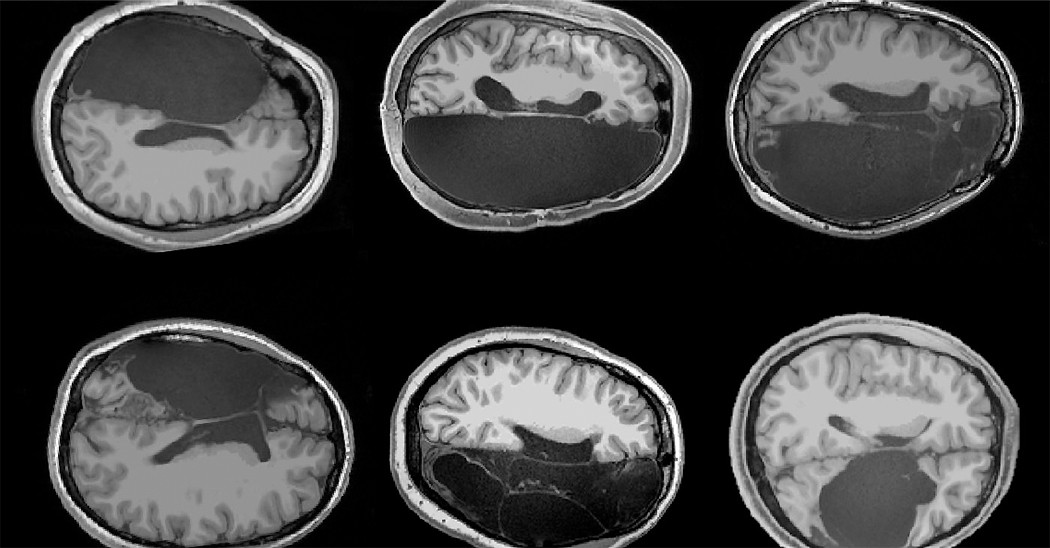

Исследовательская группа провела магнитно-резонансную томографию (МРТ) пациентов, которые перенесли операцию гемисферэктомию в детстве и теперь имеют относительно нормальные когнитивные способности. Сканирование пациентов сравнивалось со сканированием здоровых людей.

Результаты показали, что мозговые сети у пациентов с гемисферэктомией — которые контролируют ходьбу, разговор и другие функции — были на удивление целы.

«Несмотря на то, что у них отсутствует целое полушарие мозга, мы обнаружили все те же основные сети, что и в здоровом мозге с двумя полушариями», — говорит Дорит Климанн (Dorit Kliemann), ведущий автор нового доклада и доктор наук из центра визуализации мозга Caltech (Caltech Brain Imaging Center).

Исследователи обнаружили, что у взрослых, у которых в детстве было удалено одно

полушарие головного мозга, замечательно сохранена организация функциональных мозговых сетей в оставшемся полушарии.

Исследователи выбрали для анализа не весь мозг, а лишь те районы, которые отвечают за зрение, внимание, движения тела и некоторые другие. Как пишут авторы работы, у «безполушарных» людей связи между этими центрами оказались намного сильнее, чем у людей с обоими полушариями. Например, у участков коры, которые отвечают за ходьбу, было больше каналов связи с участками коры, регулирующими речь. Сама по себе сеть соединений была такой же, как в обычном мозге, только нервные центры, входящие в эту сеть, у «безполушарных» людей общались друг с другом гораздо более плотно.